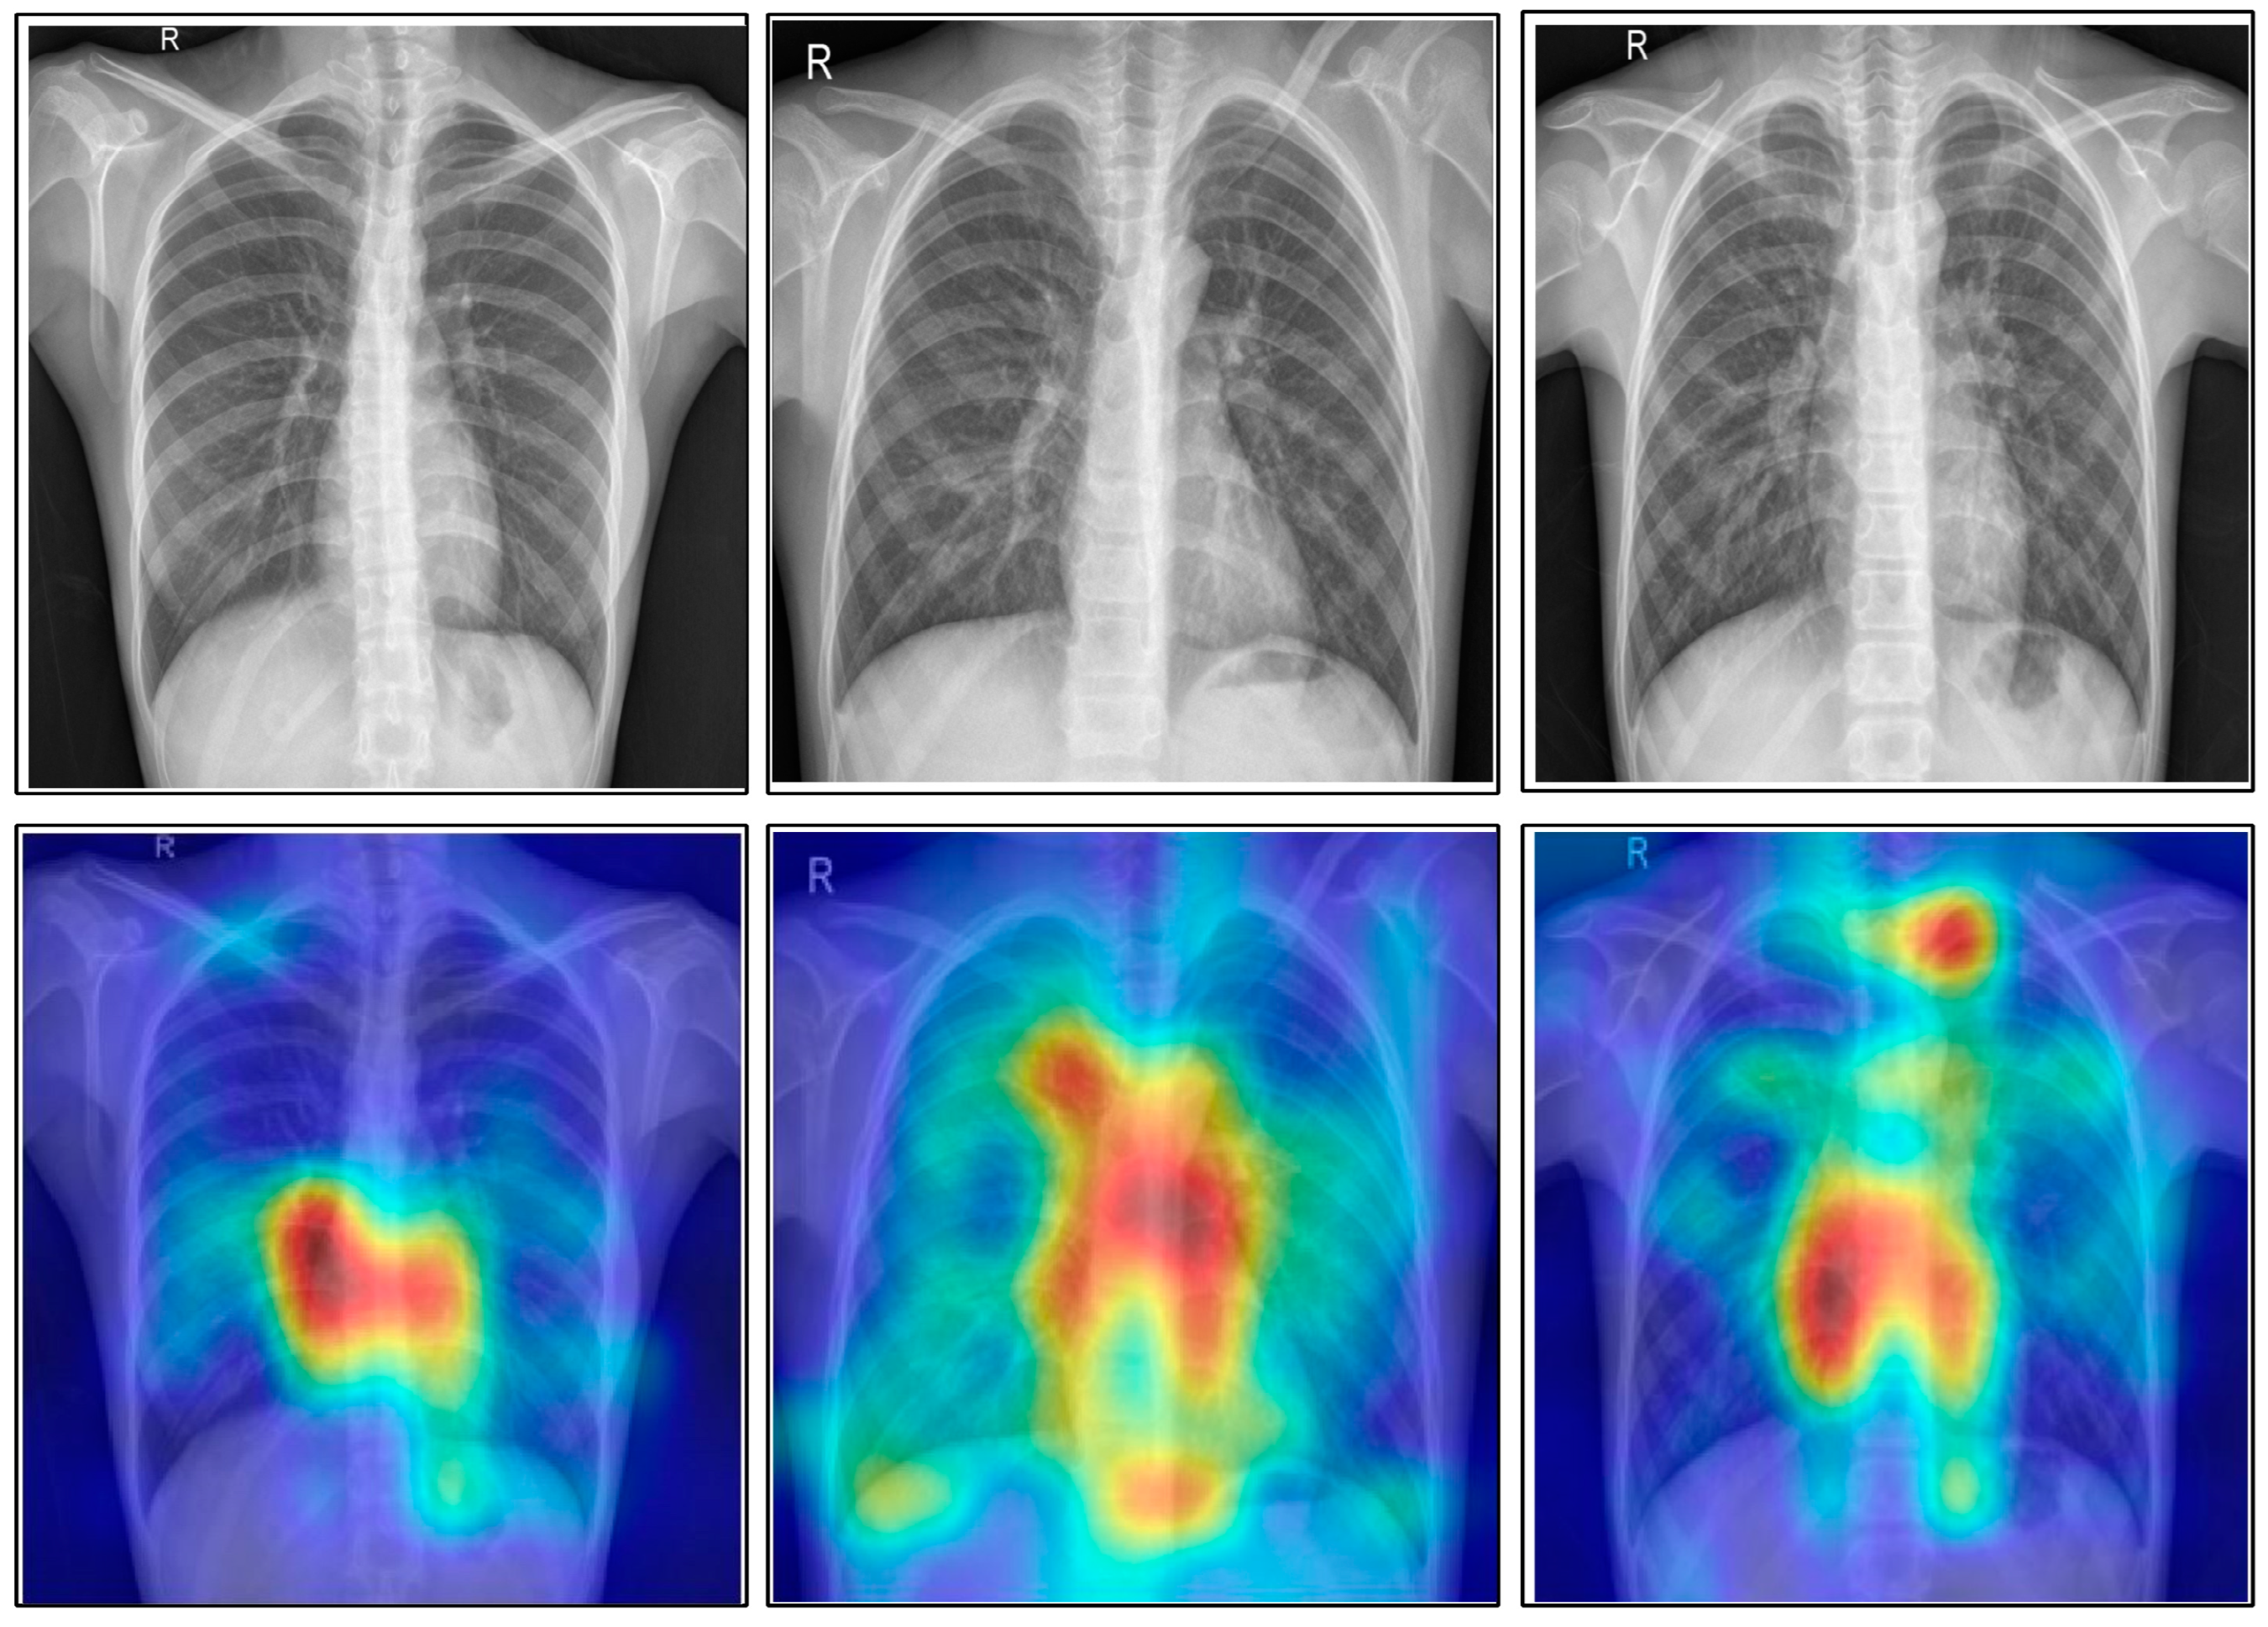

A comprehensive comparison was conducted with several recent techniques, as is shown in Table 13. Several latest released techniques are included in this table, and they all used the deep learning architecture. Recently, the highest recorded accuracy was 99.2%. Our framework tested on five publically available datasets achieved accuracies of 99.6, 98.5, 99.9, 99.5 and 100%. Moreover, the in-depth analysis among original CCA and ICCA was conducted at the end to show the change in accuracy after the improved fusion method. Table 14 shows the results of this process, and it was observed that the accuracy of the ICCA was improved, but the time also increased slightly. Overall, the ICCA-based fusion approach showed the most improvement. Moreover, Figure 16 shows the impact of the data augmentation process. This figure illustrates that the accuracy of the proposed framework was improved after the data augmentation. In addition, Figure 17 illustrates the infected region visualization using the Grad-CAM approach on the proposed framework.

Figure 17.

Grad-CAM-based infected region visualization.